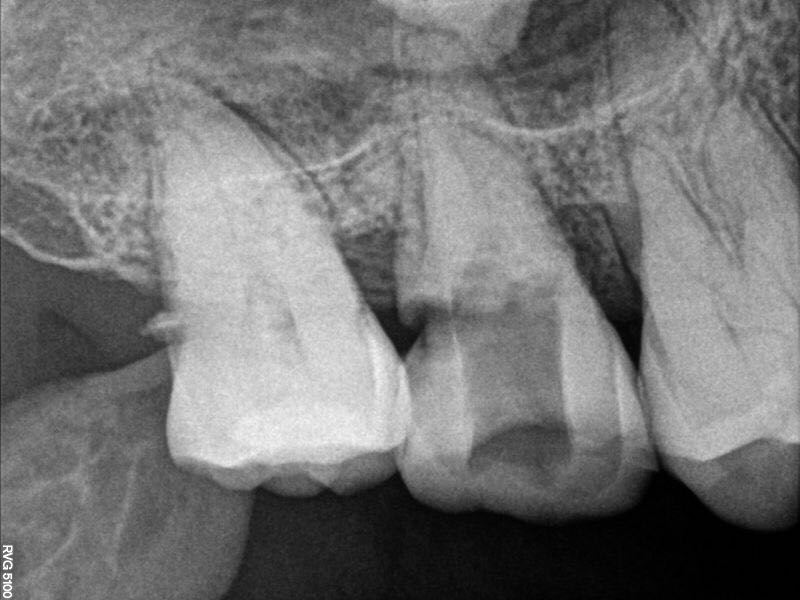

17牙冷++,叩+-,远中探及龋坏,x线片远中大面积龋坏近髓腔,根尖未见明显暗影,髓腔内大面积钙化影像

行17牙局麻下开髓失活,两周复诊,去封后见髓腔内大块髓石,p5超声去除大块髓石,根管口完全堵塞,继续去除髓石致近中壁侧穿

行近中壁侧穿修补,之后在显微镜下ET20暴露根管口,三根,均行疏通,扩锉根充

此病例,最大的难点就是髓石堵住根管口,导致根管异常难以进入,显微镜在复杂根管治疗这方面确实非常优秀。另外这个病例会侧穿主要还是太大意了,以为用了超声就万事大吉,慎之慎之